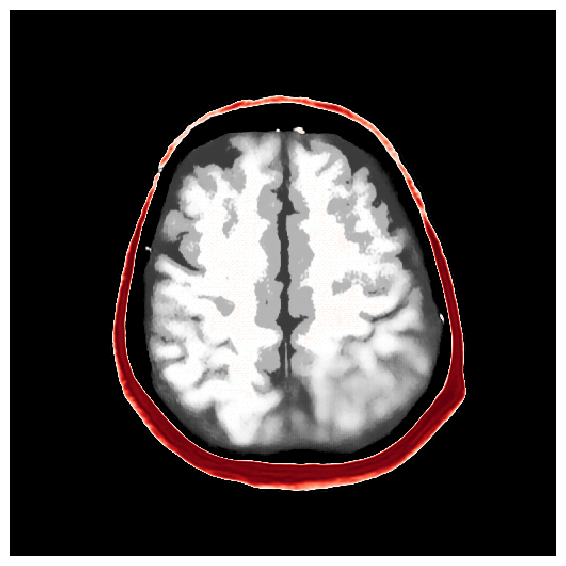

4.5 Amortized inference with iterative refinements

After the refinements of ASPIRE 2, significant improvements are evident in the posterior samples, particularly in capturing the structures within the brain tissue itself. The mean of these posterior samples, displayed in Figure 10, is clearly enhanced in resolution and details. We attribute these enhancements to the increased informativeness of the summary statistic in the second iteration compared to the information yielded by the initial iteration. A detailed inspection of the second summary statistic (shown in Figure 8) reveals more detail on the internal brain structures. Unlike the first summary statistic (cf. Figure 8), which primarily delineated the skull, the second iteration’s summary statistic better ‘illuminates’ the softer tissues within the brain, offering a more informative image for the posterior network. Thanks to accounting for the scattering at the skull, the acoustic illumination of the brain is improved significantly. Accurately resolving the skull structure is an important consideration as noted by [65].

As one can observe from Figure 10, the reconstruction quality improves for increasing number of refinements of ASPIRE. By virtue of the iterative recalculation of the score-based summary statistic, the method is progressively able to discern finer details within the brain albeit the updates become less pronounced as the number of refinements increases. We further illustrate this refinement by plotting posterior samples from all four ASPIRE iterations in Figure 21. Practically, a user of ASPIRE can decide on the number of refinements based on the amount of compute available or by refining until there are diminished returns on enhancements.